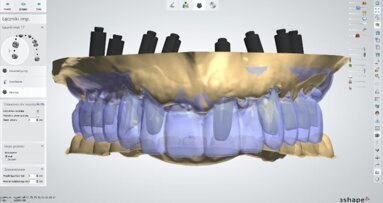

Docięty łącznik na modelu z maską dziąsłową laboratorium przekazało do gabinetu, gdzie następnie na modelu uzupełniłem żywicą przestrzeń pomiędzy łącznikiem a maską dziąsłową (Ryc. 22). Następnie przykręciłem łącznik wg klucza protetycznego w ustach pacjentki i nałożyłem na niego wcześniej przygotowany pierścień z żywicy podpierający dziąsło (Ryc. 23) i doszlifowałem go wiertłami wg standardów preparacji pod korony pełnoceramiczne (Ryc. 24-27). W pracowni pierścień ten został zeskanowany i wg niego zaprojektowano czapkę cyrkonową pod koronę ceramiczną (Ryc. 28 i 29).

Profil ukształtowany przez koronę tymczasową zespoloną z łącznikiem tymczasowym został tym samym precyzyjnie odtworzony w pracy ostatecznej. Taki protokół postępowania był możliwy dzięki pracy w systemie CAD/CAM. Dlatego po zacementowaniu korony na implancie wygląd dziąsła przy nim był bardzo zbliżony do kształtu dziąsła przy zębie jednoimiennym. Różnica w kolorze, która pozostała spowodowana jest niestety, trwałym tatuażem po zaaplikowaniu amalgamatu przed laty.